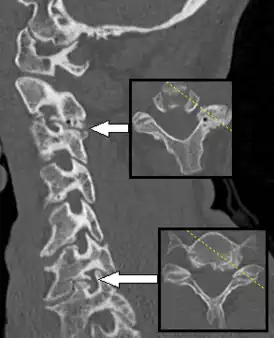

КТ спондилёза, вызывающего радикулопатию

Спондилёз (spondylosis; греч. «spondylos»- позвонок; син. деформирующий спондилёз) — инволюционный процесс постепенного изнашивания и старения анатомических структур позвоночника, сопровождающийся дистрофией наружных волокон передних или боковых отделов фиброзного кольца, выпячиванием его под давлением сохранившего свой тургор мякотного ядра, отложением и оссификацией передней продольной связки и образованием краевых костных разрастаний (остеофитов) вдоль оси позвоночника только по окружности передних и боковых отделов.

При спондилёзе костная ткань суставов разрастается, образуются остеофиты, то есть дополнительная костная ткань (по мере нарастания костный вырост распространяется к соседнему позвонку, тогда как от соседнего позвонка образуется такой же вырост, в некоторых случаях окостенение начинается на уровне межпозвоночного диска). В особо тяжёлых случаях наступает сращение позвонков, от чего страдают сосуды, нервы и мышечная ткань, а также близлежащие органы.